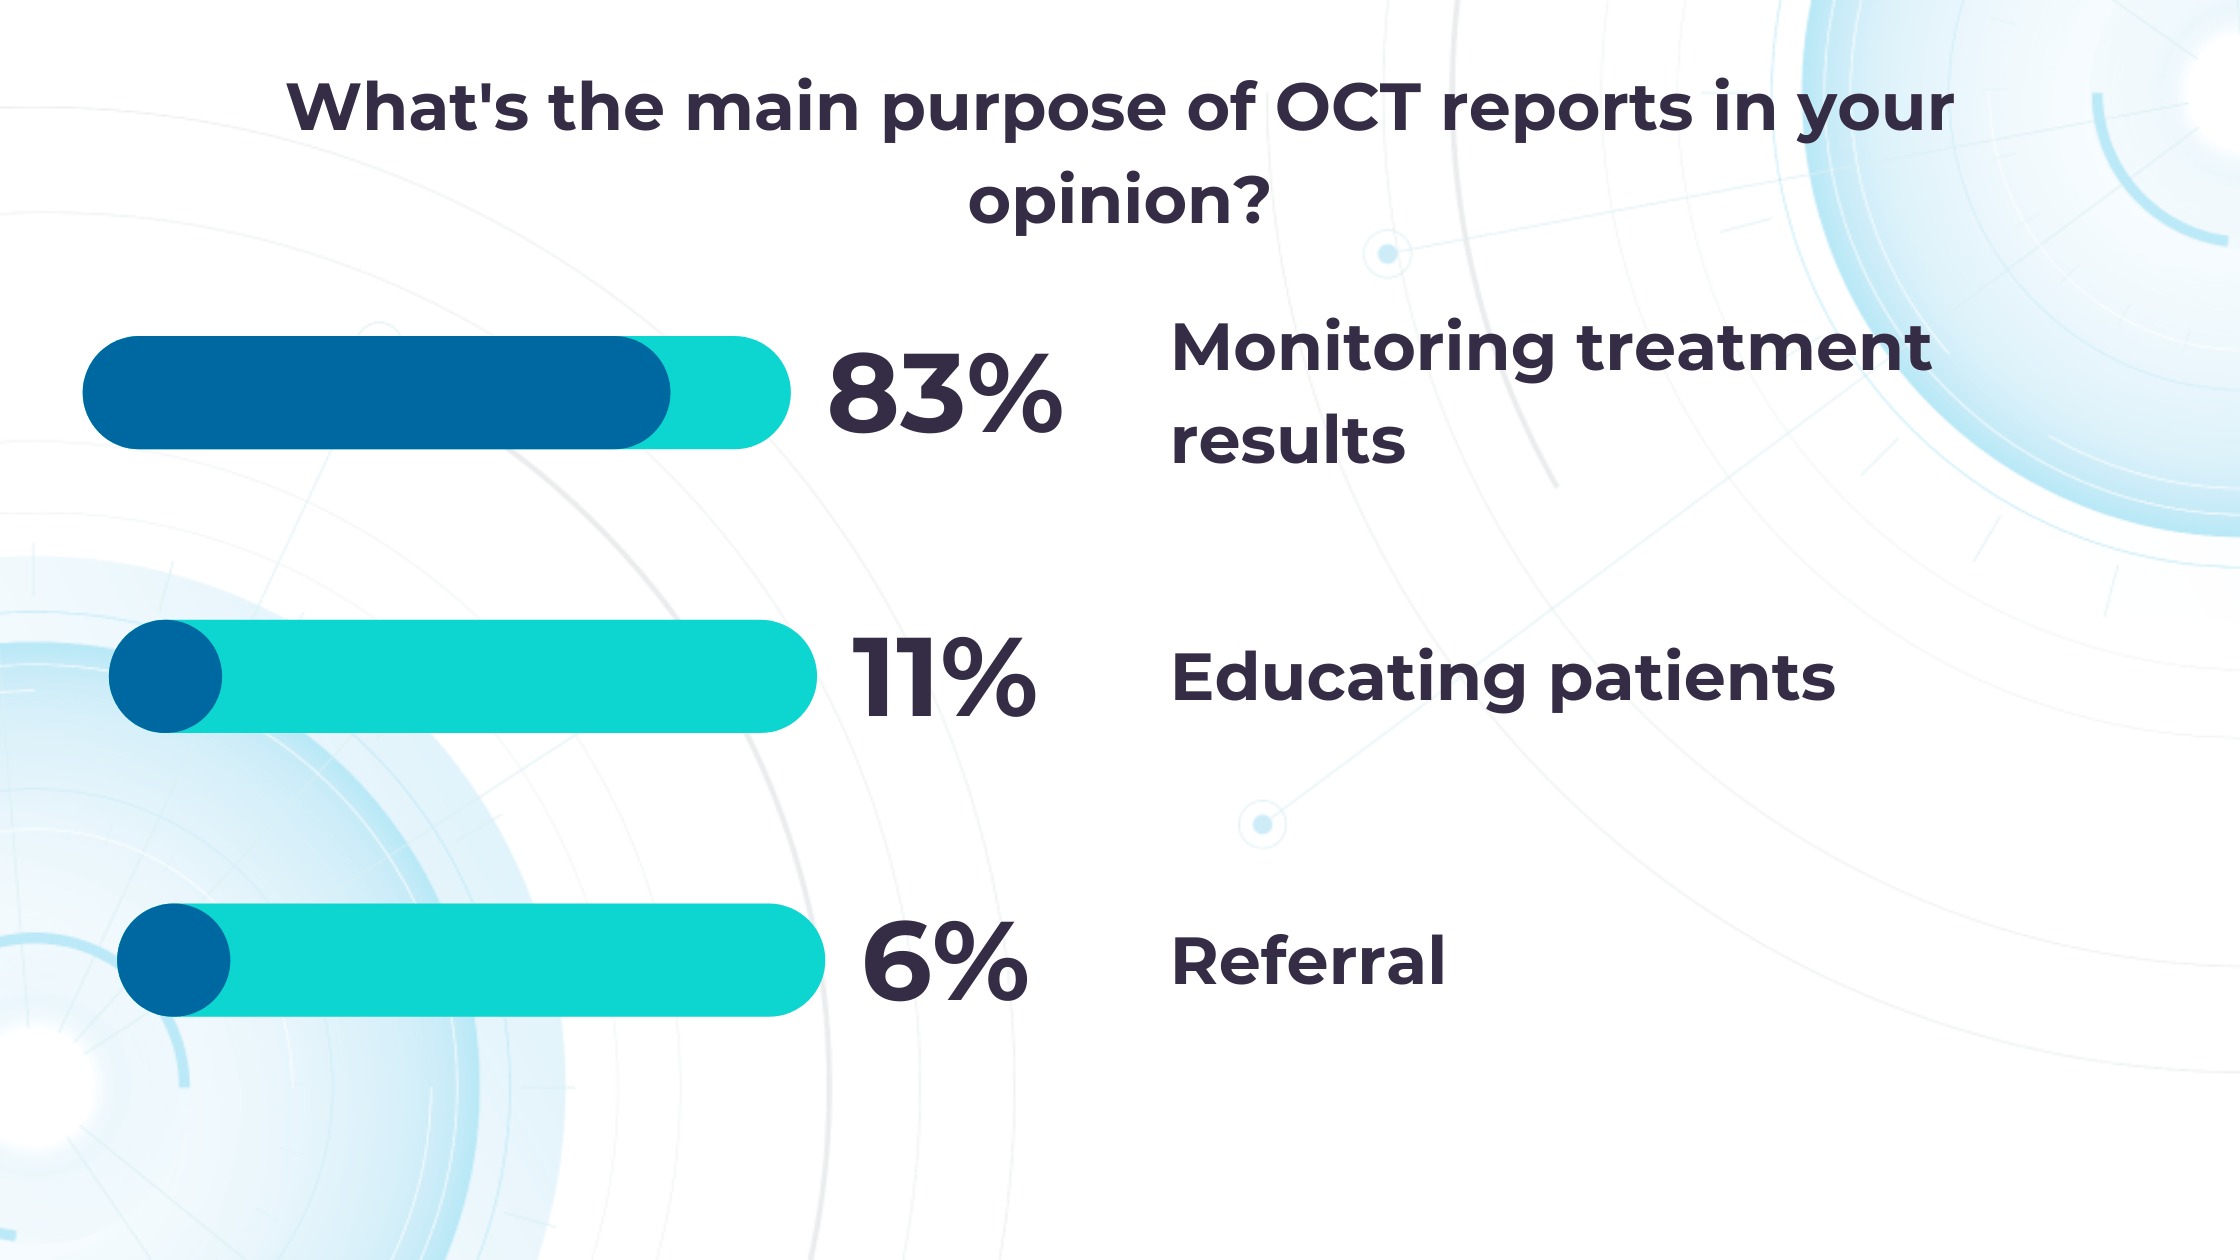

Altris AI’s recent survey has revealed that the key benefits of OCT technology for eye care specialists lie in treatment monitoring, patient education, and referral optimization.

-

Measuring treatment progress: biomarkers tracking, pathology progression